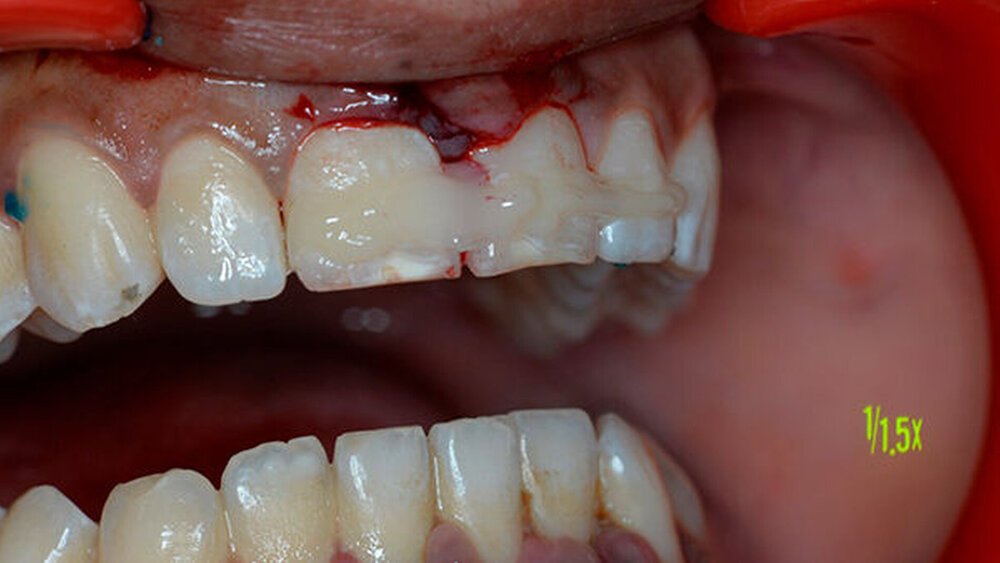

Der Patient hatte Glück im Unglück: Er fand den Zahn im Schnee. Und wickelte ihn sorgfältig in ein Papiertaschentuch. Dann transportierte er ihn unter für das desmodontale Gewebe ungünstigen Bedingungen in die Praxis.

Der Zahn wurde zwei Stunden nach dem Unfall vital replantiert und semipermanent geschient. Die anschließende Abdrucknahme erfolgte unter allergrößter Sorgfalt. Die laborgefertigte Tiefziehschiene schließt die Bereiche der semipermanenten Schiene bis zum Schienenäquator mit ein. Was die Reanastomosierung der Gefäße und Nerven betrifft, ist der Behandler zuversichtlich, reagieren doch auch vital transplantierte Weisheitszähne nach einigen Wochen wieder auf Kältereize.